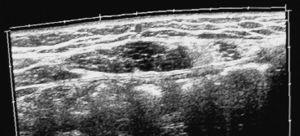

Aporta diferentes exploraciones complementarias: una ecografía abdominal, una ecografía ginecológica, una ecografía musculosquelética, una tomografía computarizada (TC) abdominal, una gammagrafia ósea planar, una resonancia magnética (RM) y un análisis sanguíneo. En la TC abdominal se observa una imagen patológica en el músculo rectus abdominis izquierdo, compatible con una cicatriz muscular (fig. 1). En la ecografía ginecológica se aprecia un quiste folicular en el ovario derecho, al que el ginecólogo no da importancia. En la ecografía musculotendinosa se ven 2 cicatrices fibrosas en el músculo rectus abdominis izquierdo a diferente nivel (fig. 2).

Figura2